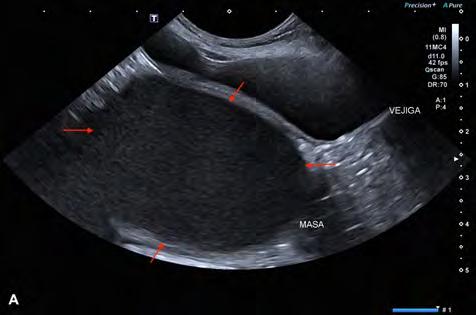

Se excluyeron del estudio los pacientes con patologías concomitantes a la ECDM, tanto cardíacas como de otros sistemas orgánicos, excepto la presencia de hipertensión pulmonar estimada mediante ecocardiografía. Se realizó la medición del volumen del atrio izquierdo con el método monoplano sumatorio de discos (MOD)9 a partir de la técnica de Simpson, que consiste en la medición del volumen del AI mediante la suma de los volúmenes de diferentes discos contiguos perpendiculares al eje mayor del AI generados por el software del ecógrafo, tras trazar el área del AI y su eje mayor de forma manual. Esta medición se realizó desde el corte paraesternal derecho longitudinal de 4 cámaras en telesístole, previo a la apertura de la válvula mitral (Fig. 1). Se siguió el borde endocárdico del atrio izquierdo, previo a la apertura de la válvula mitral en la telesístole cardíaca, sin incluir las venas pulmonares. Posteriormente, lo correlacionamos con el peso del paciente realizando la ratio: LAv/BW = volumen del atrio izquierdo (ml) / peso del paciente (kg).1,2,6

Figura 1. ECDM. (A) Medida mediante MOD del volumen del AI. (B) Corte paraesternal derecho 4 cámaras, zoom AI. Ratio LA/BW = 3, 8 ml/kg.